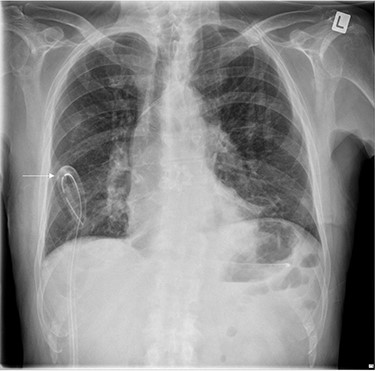

The left basal chest drain was removed without incident on Day 5. However, the nurse encountered resistance during attempted removal of the right basal chest drain. The intern was subsequently notified. Resistance was also encountered by the intern during a further attempt to remove the chest drain. A chest X-ray performed earlier in the day was reviewed (Fig. 2). It demonstrated kinking of the drain around a rib. The intern altered the direction of traction in order to account for the kinking but, during gentle traction, the chest drain fractured at the 14-cm mark (Fig. 3) and became retained within the right hemithorax (Fig. 4). The thoracostomy wound was closed and senior help was immediately sought.

Chest X-ray demonstrating the retained chest tube segment on the right side.